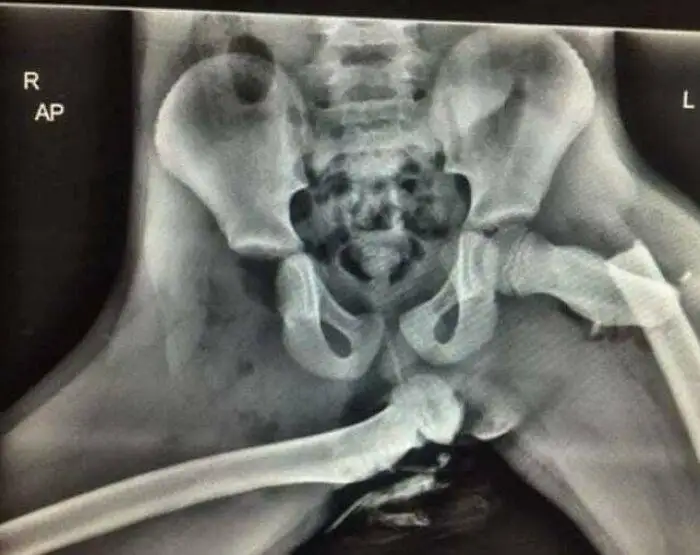

در مقاله دیگری در برترین ها کاربرانی با سابقه کار در اورژانس درباره خطر قرار دادن پاها روی داشبرد در خودرو هشدار داده بودند. در این تصویر اشعه ایکس یکی از سرانجام های ترسناک و دردناک انجام چنین حرکتی پیش از تصادف را مشاهده می کنید.